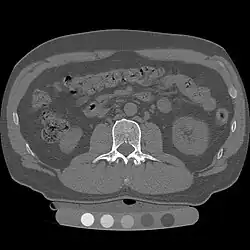

Quantitative computed tomography (QCT) is a medical technique that measures bone mineral density (BMD) using a standard X-ray computed tomography (CT) scanner with a calibration standard to convert Hounsfield units (HU) of the CT image to bone mineral density values.[1] Quantitative CT scans are primarily used to evaluate bone mineral density at the lumbar spine and hip.

Originally, conventional 2D QCT used individual, thick CT slice images through each of multiple vertebrae which involved tilting the CT scanner gantry to align the slice with each vertebra. Today, modern 3D QCT uses the ability of CT scanners to rapidly acquire multiple slices to construct three-dimensional images of the human body. Using 3D imaging substantially reduced image acquisition time, improved reproducibility and enabled QCT bone density analysis of the hip.[1]

QCT scan protocols are low-dose and can limit the amount of radiation exposure to between 200-400μSv for a spine exam[6] This is comparable to a set of mammograms and typically substantially less than a standard CT exam. Using other non-IV contrast abdominal or pelvic scans such as a Virtual Colonography studies, the QCT exam can be performed without requiring any further image acquisition or consequent radiation dose to the patient.[7]

Dual use of CT images

Several studies have shown that bone density may be measured by QCT using CT images that were ordered for other purposes. Using pre-existing images, including CT colonography exams,[14] QCT allows for bone density screening without submitting the patient to any additional radiation exposure. The feasibility of using routine abdominal contrast-enhanced CT scans for the evaluation of bone density by QCT has also been demonstrated.[15]